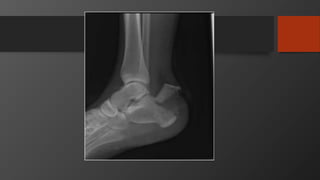

Ankle Fractures

Imaging

• AP, Lateral

• Mortise view

• CT scan

• Especially posterior malleolus